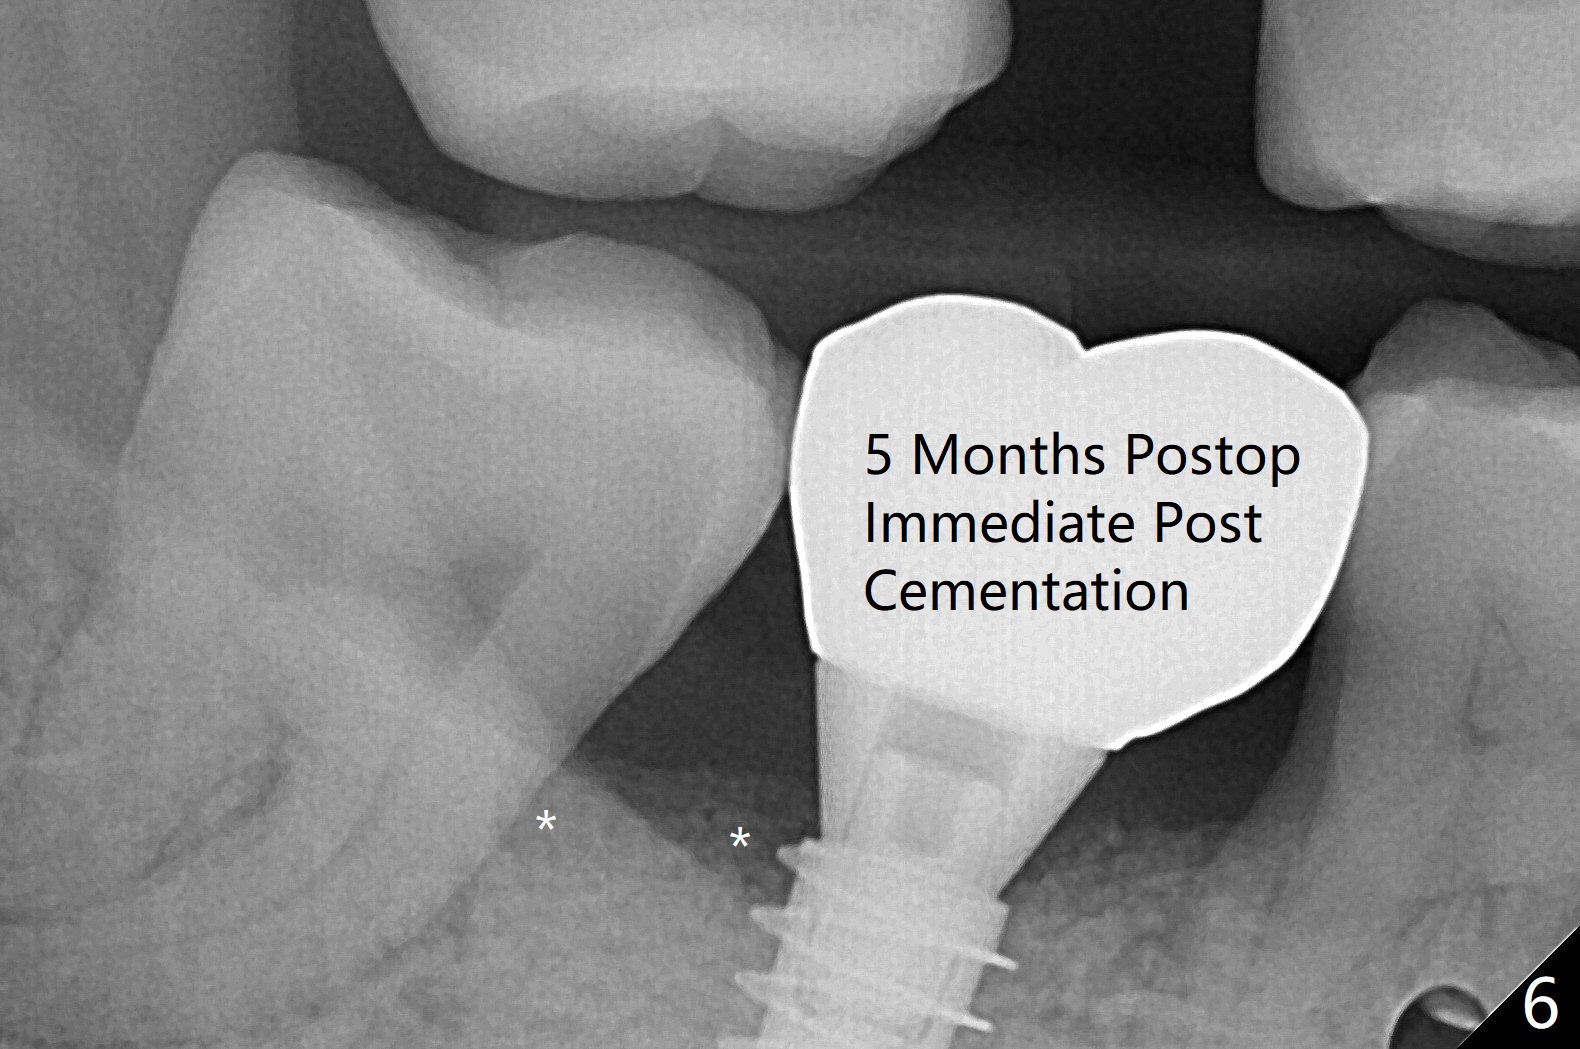

右下7有两个融合牙根,很长,起初(拔除后)有点害怕初步稳定性,使用导板完成近中窝4x10毫米钻洞后,植入4.5x10毫米报废植体,当时没有发觉植体已经发生远中偏移(图一:箭头,因为近中牙槽嵴高(*),而中隔缺失)。当正式植体植入后(图二),病人发现偏移,术者觉得临床上还可以,以为可能因为X光拍摄角度问题。再次放入粘性骨粉后,咬翼片拍摄注意角度问题,但是偏移仍存在(图三)。为了防止偏移现象,要么设计时有意往阻力大的地方偏移少许(例如这个病例1毫米,图四),要么发现偏移后,有意使用侧方切割钻头(Lindamann bur)去除阻力(近中骨)。如果扭力低,包埋植体。术后一个月取出临时牙冠,骨粉仿佛成为牙龈一部分(图五:*),之后暂时粘固粉固定牙冠。术后五个月骨粉好像与邻牙牙根和植体愈合(图六:*)。永久性粘固后,基台螺丝拧紧20Ncm。